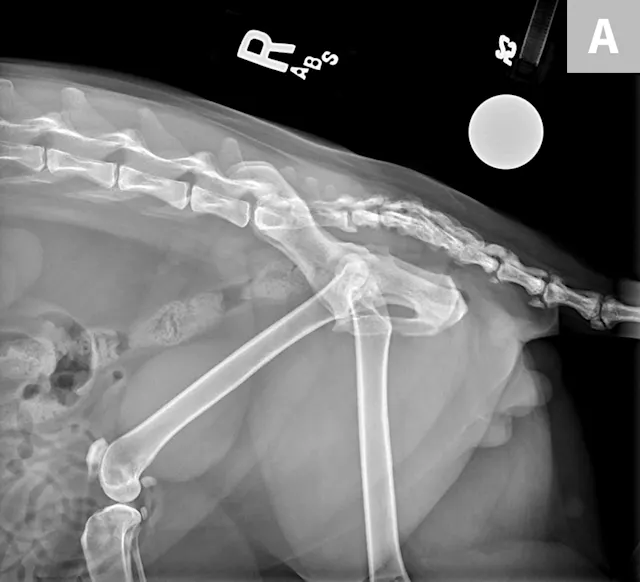

Based on clinical and radiographic findings (Figures 3-6), degenerative joint disease (DJD) involving the hips and elbows bilaterally and the right stifle, with myofascial pain in the dorsolumbar area, was diagnosed.4

FIGURE 3

Lateral (A) and dorsoventral (B) views of the pelvis. Figure A shows a moderate amount of the smoothly marginated, bridging, bony proliferations surrounding the 2nd through 5th coccygeal vertebrae. A moderate amount of kyphosis is present on the tail, centered in the bony proliferation. A mild amount of irregularly marginated bony proliferation is present surrounding the facet joint of the C5-C6 intervertebral disk space. Figure B shows poor coverage of the right femoral head by the acetabulum. A moderate amount of irregularly marginated bony proliferation is present on the cranial and caudal aspects of the acetabulum and femoral neck. There is decreased soft tissue associated with the left pelvic limb as compared with the right. A small osteophyte on the left cranial acetabulum can be noted. Image courtesy of Dr. Karen Perry. Interpretation: Chronic, healed caudal vertebral fracture, C2-C4. Moderate, right coxofemoral osteoarthritis and mild left coxofemoral osteoarthritis